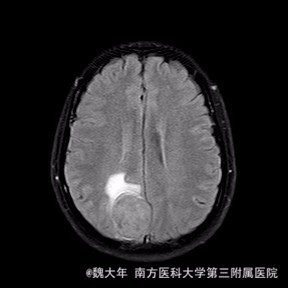

52岁,女性,因“反复头痛10余年,加重1年”入院。患者10余年前无明显诱因始出现头痛,表现为全头发作性胀痛,反复发作,无伴头晕、恶心,无呕吐、肢体抽搐,自行服药(具体不详)及休息后缓解,未予特殊处理。1年前患者觉头痛逐渐加重,以右顶部为甚,劳累或日晒后加重,无头晕、视物旋转,无恶心、呕吐,无发热、寒战,休息或平躺后症状稍有缓解,自行服药不能改善,至当地医院就诊,查颅脑MRI和CT提示“右侧顶部脑膜瘤”。

行“右顶开颅右顶部矢状窦旁脑膜瘤切除术”。取右顶马蹄形手术切口 ,颞侧翻开皮瓣,电刀切开骨膜,中线矢状缝上前、后极各钻一孔,颞侧后方钻一孔,铣刀铣一长方形(7*6cm)骨瓣,见硬膜表面较多点状渗血,予充分止血,悬吊硬膜。 显微镜下切除肿瘤:沿肿瘤边缘剪开硬膜后,见一大小约5*5*6cm肿瘤,沿硬膜内侧面呈匍匐状生长,边界与脑组织有蛛网膜分隔,质地较韧,基底与矢状窦关系密切,靠内侧与大脑镰粘连紧密,血供丰富。仔细分离肿瘤与脑组织的粘连,全切除肿瘤。肿瘤基底与矢窦粘连紧密,并破坏矢状窦侧壁,予低功率电刀反复烧灼,直至肿瘤无明显血供表现。严密止血后常规关颅。